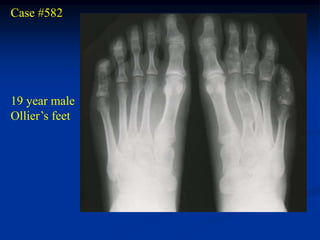

Case #582

19 year male

Ollier’s feet